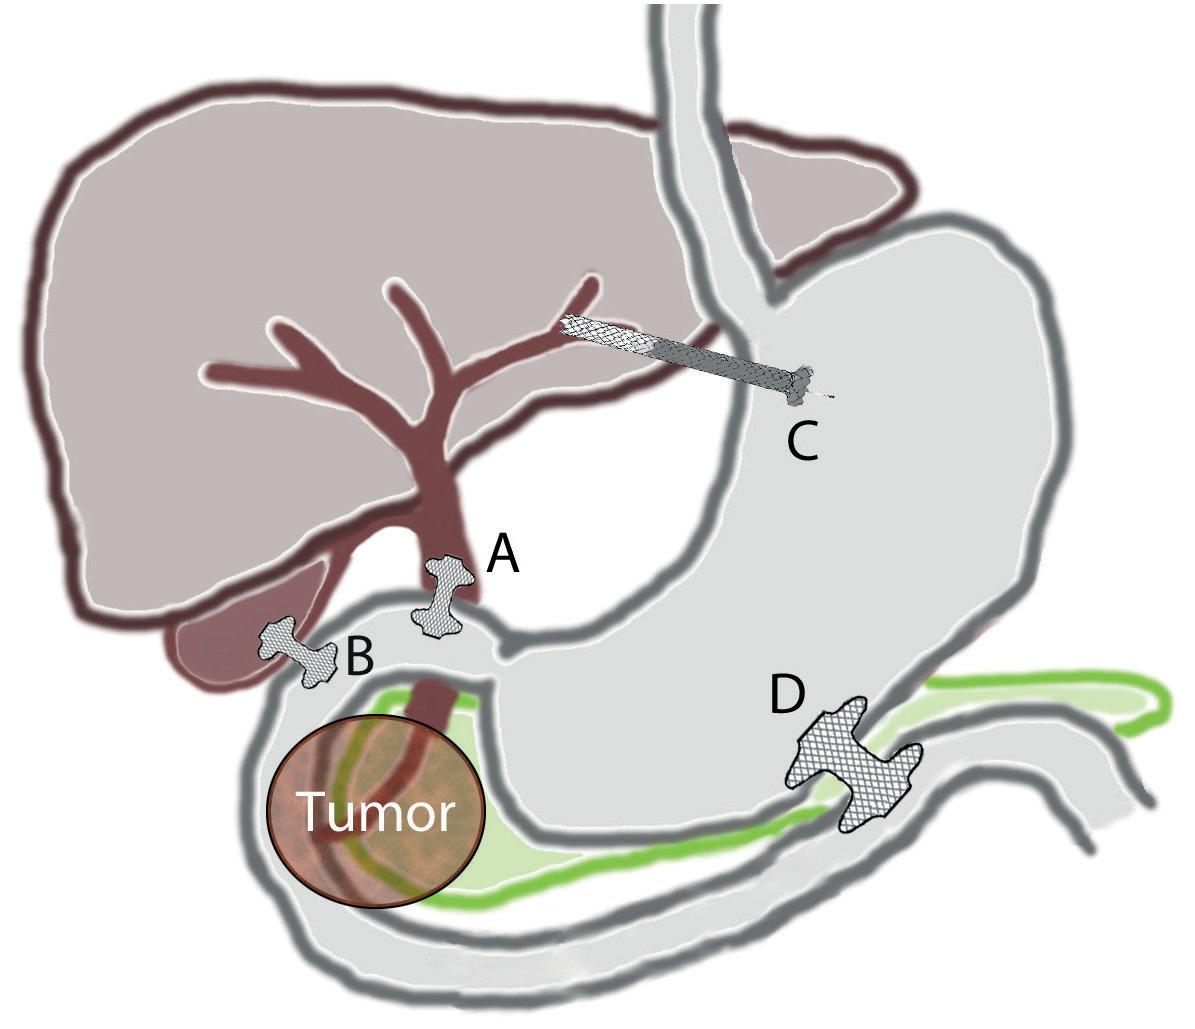

Utvikling av LAMS har også gjort det mulig å etablere EUSveiledet galledrenasje med relativt liten risiko for komplikasjoner, gitt erfaren endoskopør. Dette er spesielt aktuelt hos pasienter med periampullær tumorobstruksjon (typisk pankreascancer) som er i non-kurativ situasjon, og hvor vanlig ERCP med stent ikke er mulig. Sammenlignet med transhepatisk perkutan tilgang (PTC) synes intern EUS-drenasje med LAMS (figur 5) å gi mindre komplikasjoner, lavere risiko for reintervensjon, og mindre smerter (9). Metoden muliggjør også galledrenasje via galleblæren dersom

tilgang via gallegang ikke er mulig og det er passasje for gallen via ductus cysticus (Figur 5). Hos pasienter med perihilær obstruksjon har EUS-veiledet tilgang gjennom ventrikkelen og inn i venstre leverlapp (hepatikogastrostomi) blitt en etablert prosedyre ved større sentra. Prosedyren brukes hovedsakelig til galledrenasje der hverken konvensjonell ERCP eller drenasje via LAMS til gallegang/galleblære ikke er mulig. Ved denne prosedyren bruker delvis dekkede selvekspanderende metallstenter fra intrahepatisk gallegang til ventrikkel (figur 5). EUS veiledet galledrenasje er teknisk mer krevende enn drenasje av cyster/WON og vurdering av indikasjon og pasienten totalsituasjon er viktig. Konvensjonell ERCP er fortsatt første valg der dette er mulig.

Figur 5. EUS-veiledet drenasje og anastomose. Choledochoduodenostomi (A), cholecystoduodenostomi (B), hepaticogastrostomi (C) og gastroenterostomi (D).